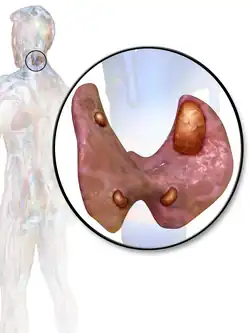

A parathyroid adenoma is a benign tumor of the parathyroid gland. It generally causes hyperparathyroidism; there are very few reports of parathyroid adenomas that were not associated with hyperparathyroidism.[1]

A human being usually has four parathyroid glands located on the posterior surface of the thyroid in the neck. In order to maintain calcium metabolism, the parathyroid glands secrete parathyroid hormone (PTH) which stimulates the bones to release calcium and the kidneys to reabsorb it from the urine into the blood, thereby increasing its serum level. The action of calcitonin opposes PTH. When a parathyroid adenoma causes hyperparathyroidism, more parathyroid hormone is secreted, causing the calcium concentration of the blood to rise, resulting in hypercalcemia.[2]